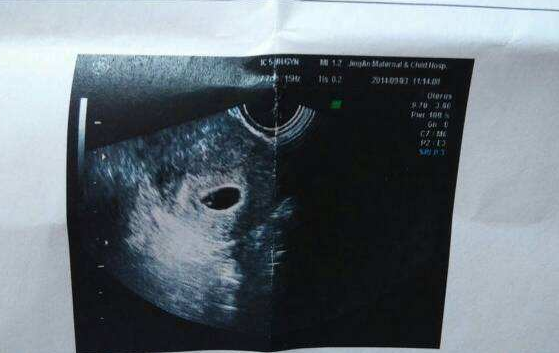

表现之三:宝宝的胎囊

大部分女人在怀孕早期的时候都会去医院做检查,每次都会去做B超,再做B超的时候,可能已经会看到很小的孕囊了。虽然说在孕早期的时候,宝宝还没有开始发育,但是如果想要提前知道孩子的性别,就可以通过孕囊的形状大概可以推测出,如果说孕囊的形状看起来比较接近长方形,而且四周有明显的凸出物体,那么怀上男孩子的可能性就会非常的高。